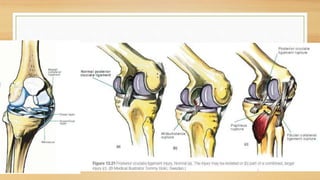

CLASIFICACION:

ANTEROMEDIAL:

Capsula medial , LCI, LCA, ligamento oblicuo

posterior

ANTEROLATERAL:

Capsula lateral, LCA, ligamento poplíteo arqueado

POSTEROMEDIAL:

LCI, capsula medial, ligamento poplíteo oblicuo

posterior, LCA, capsula posteromedial

POSTEROLATERAL:

Capsula lateral, LCA, ligamento poplíteo arqueado,

LCL